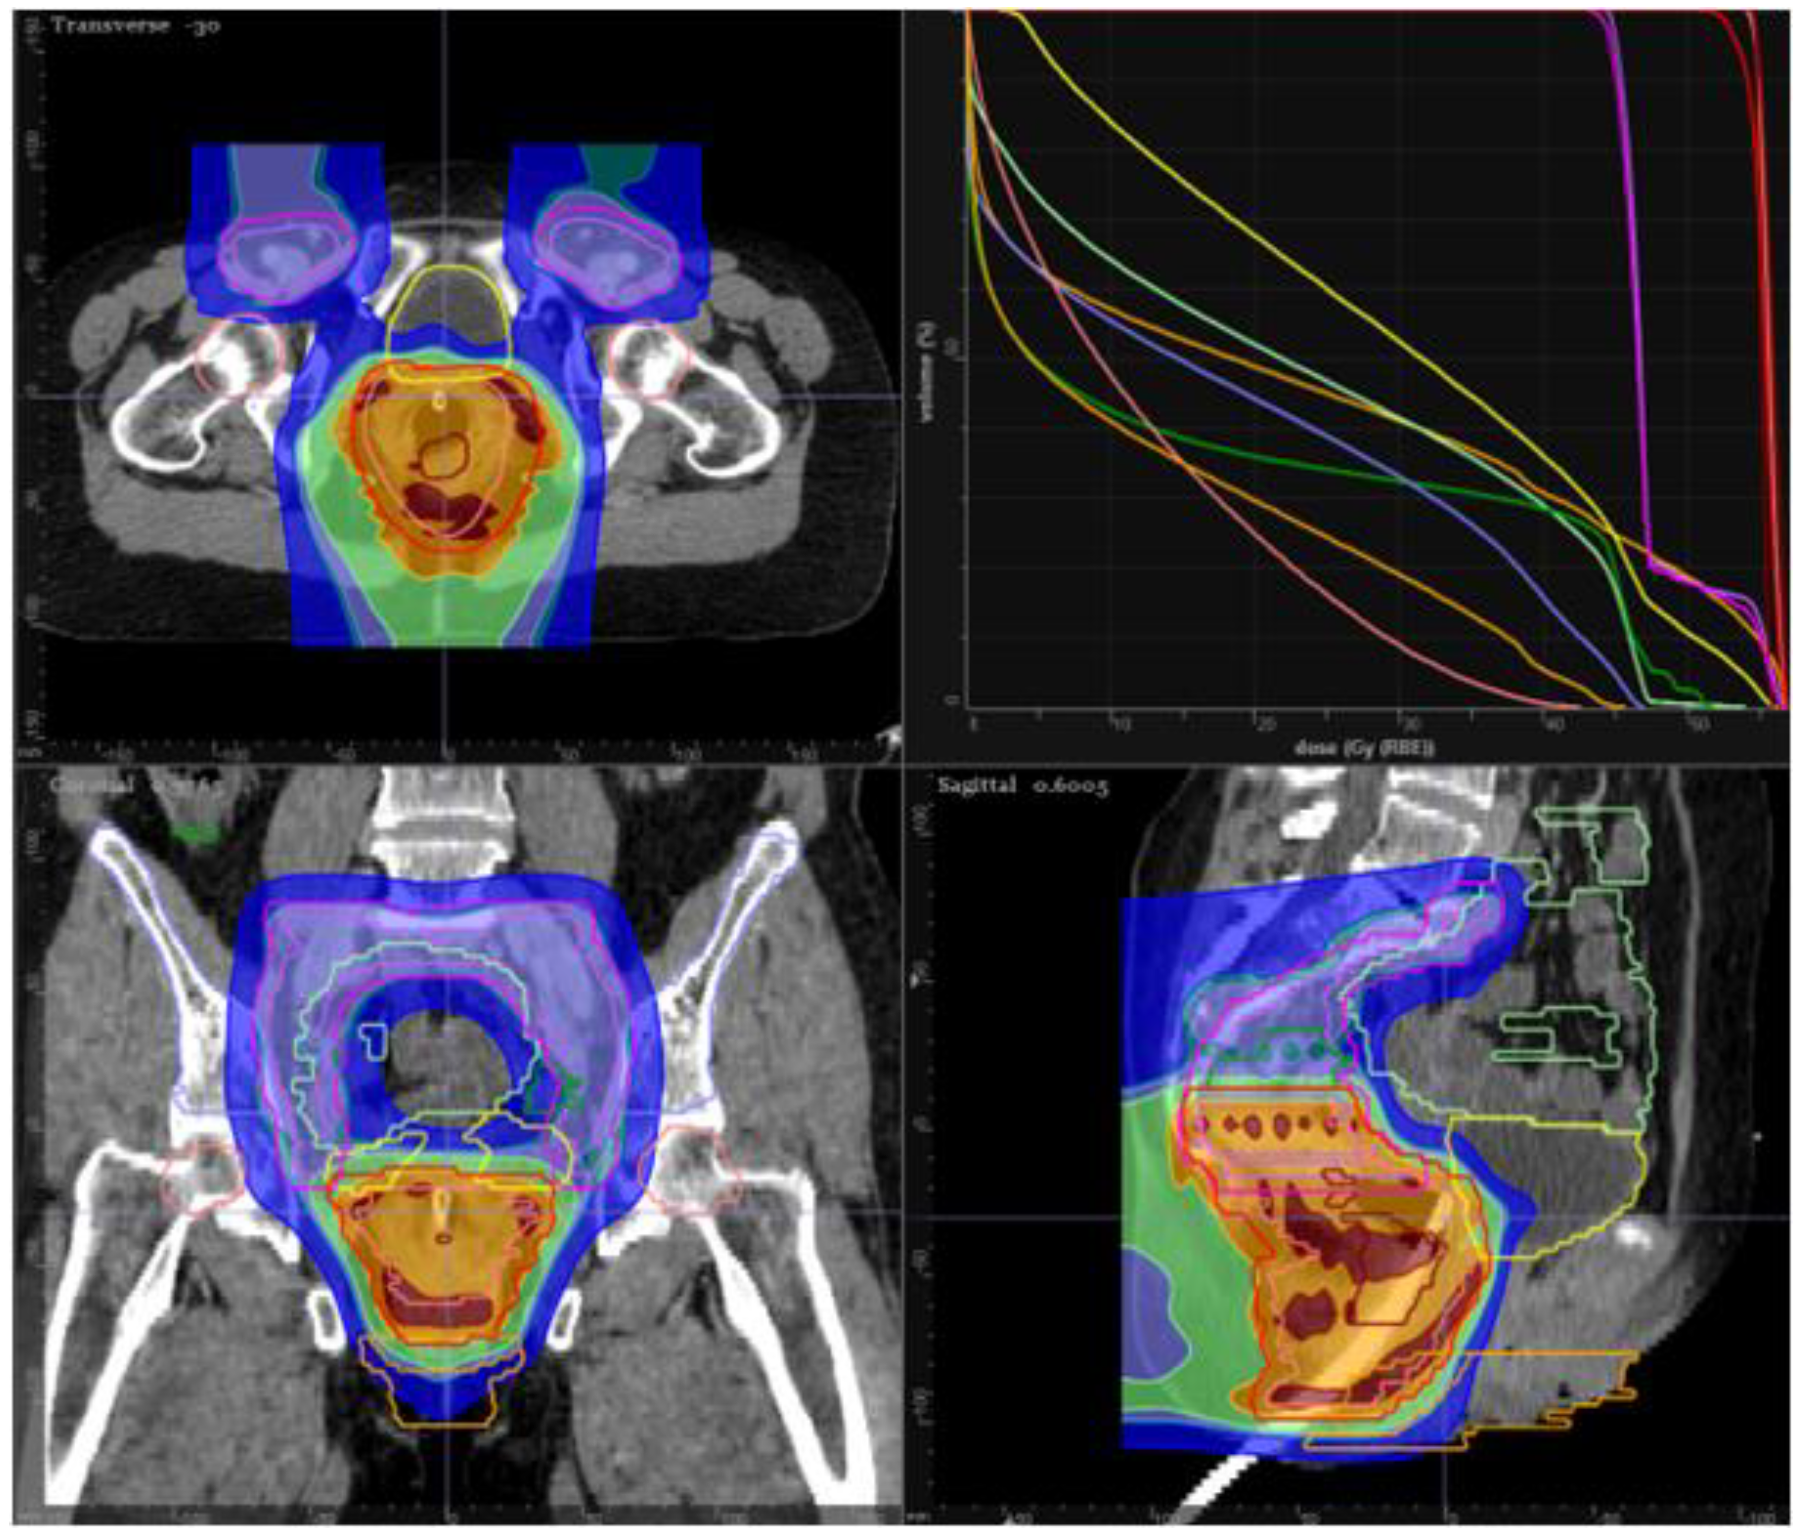

14. Proton Therapy in Anal Cancer